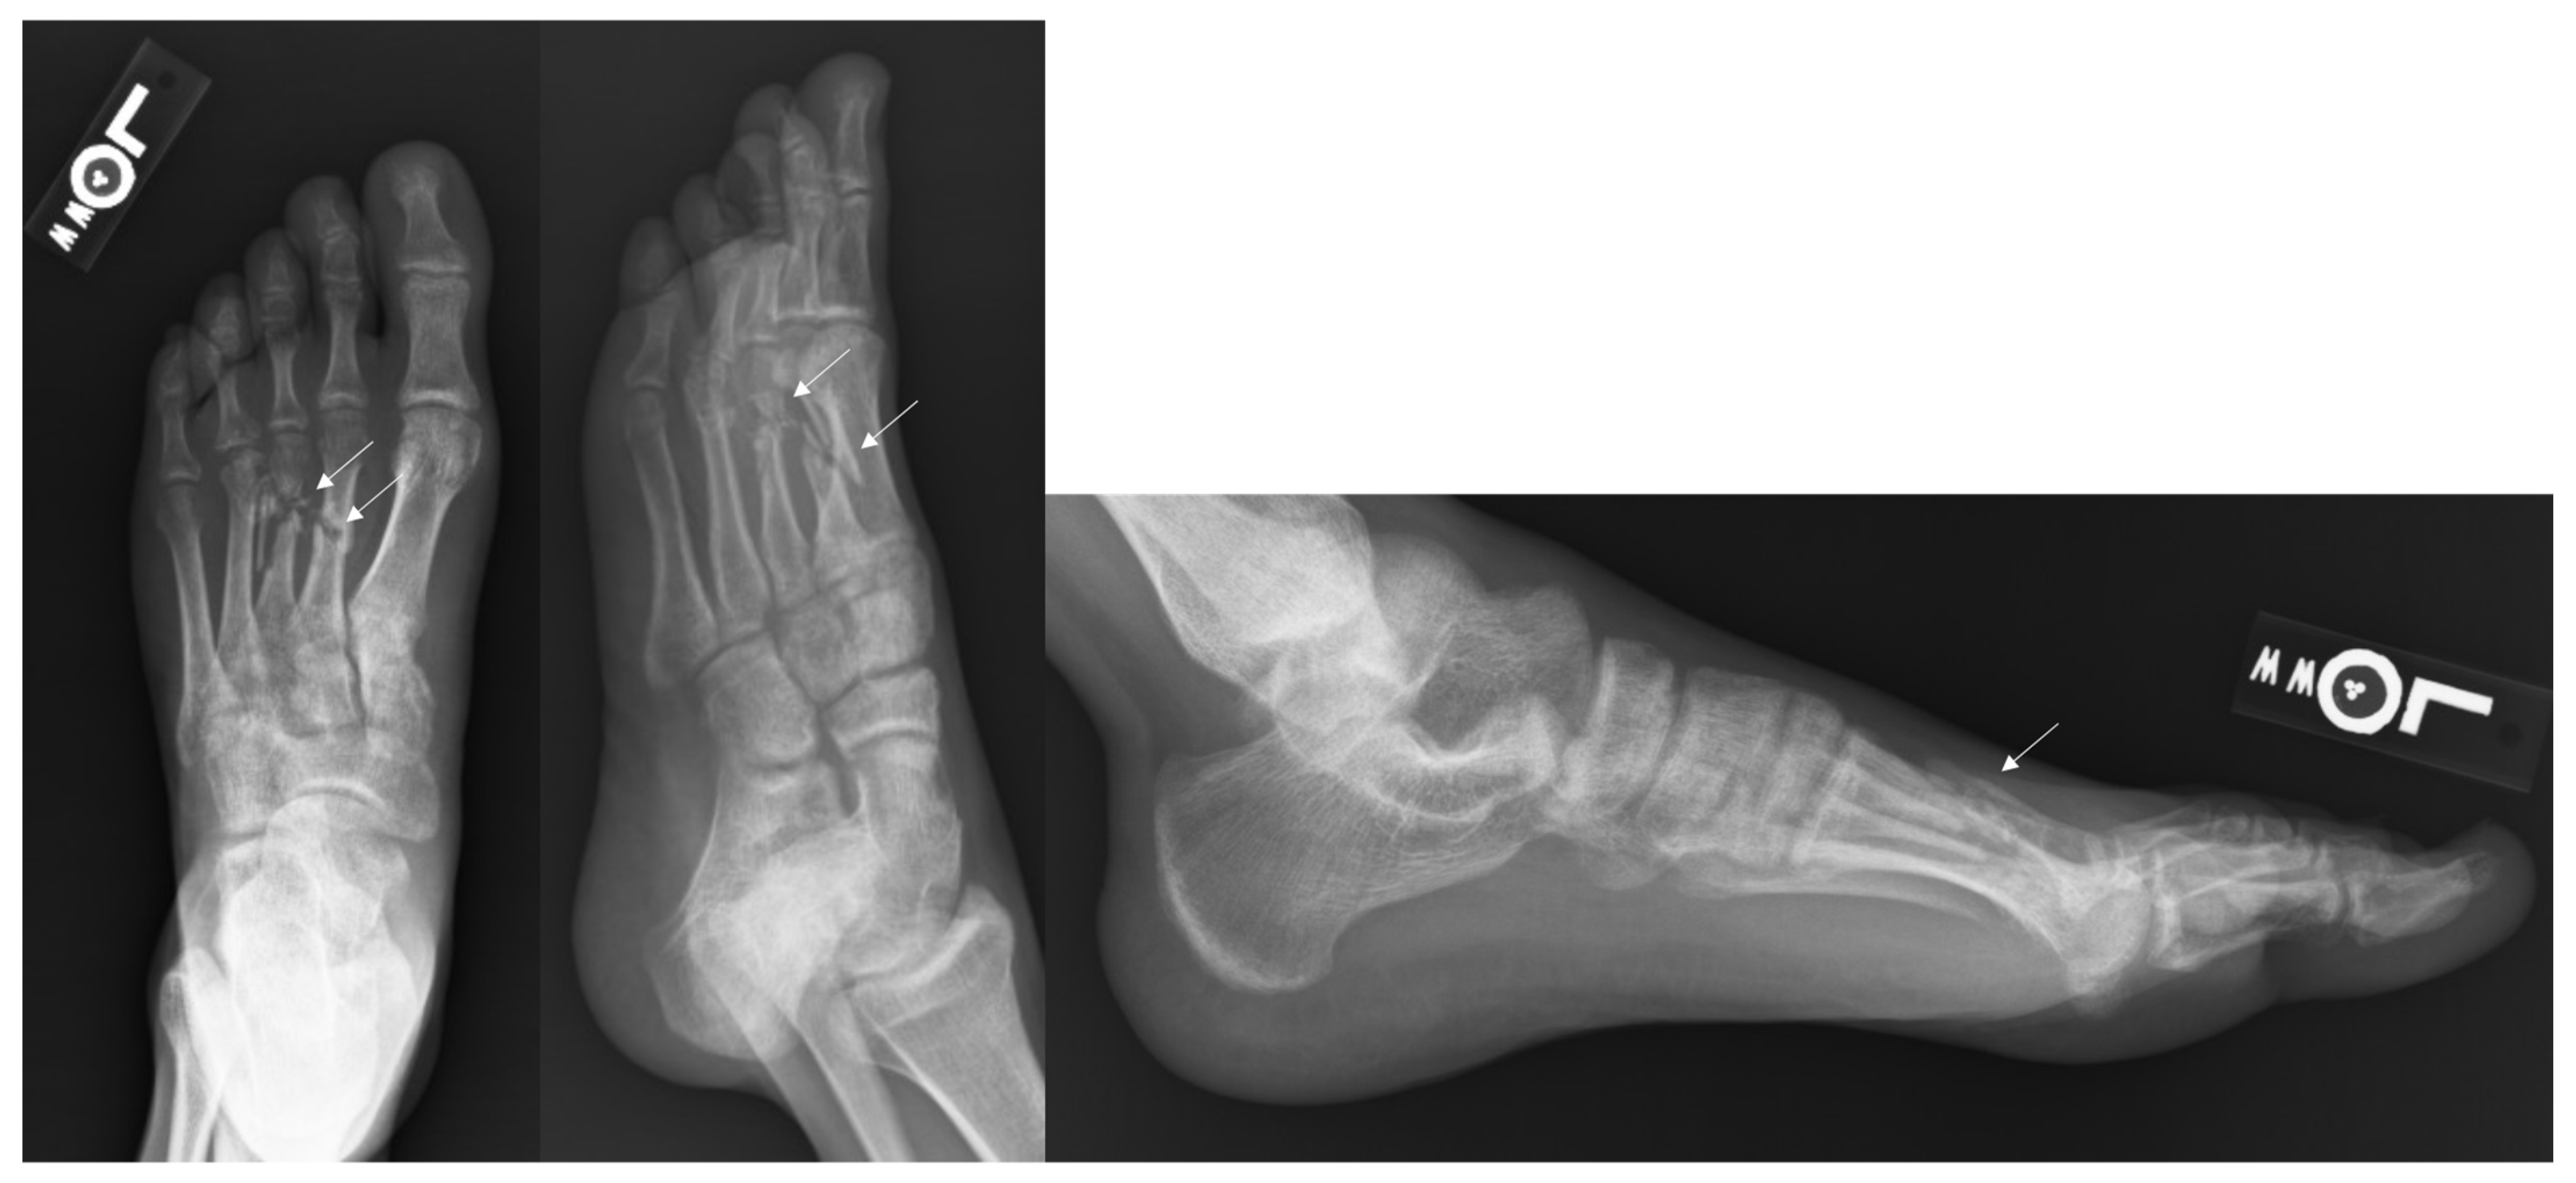

Figure 1.

Injury Films for Displaced Metatarsal Fractures from a Gunshot. Displayed above are the injury radiographs for second and third metatarsal fractures following a gunshot injury. The arrows above identify the metatarsal fractures.